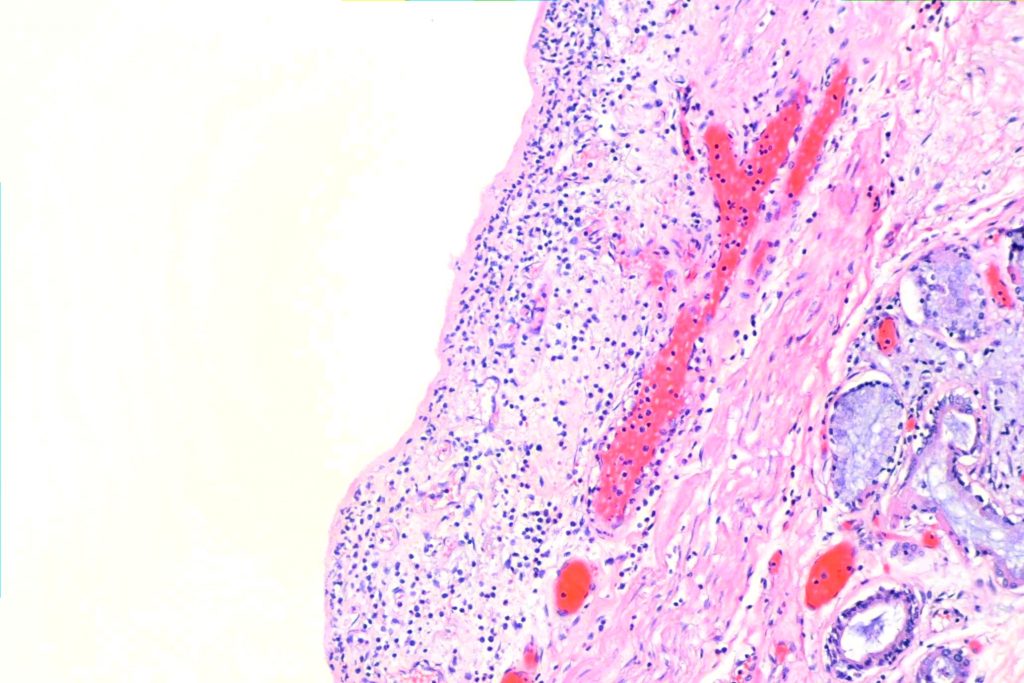

- It’s kind of patchy, so you can see “normal” places intermixed with bad fibrotic places. Here are two very low power shots of this case. There were some problems with fixing the background on the panorama shots, so I apologize for that. Nonetheless, you can see patches of relatively normal alveoli here and there. Since this was a fatal case, there weren’t all that many. Fibrosis is supposed to be at the periphery of the lobule, so you’ll see relatively normal alveoli in a patch surrounded by fibrosis. In addition, there should be distortion of the architecture of the lung.

3. While honeycomb change is a common end-stage pathway for interstitial disease, and is thus fairly nonspecific, you can find it, and it helps rule out stuff that doesn’t have honeycombing. Often the spaces are lined by respiratory epithelium (“bronchiolar metaplasia”) and can be filled with mucous.